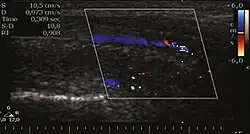

Venous drainage is performed by the deep and superficial dorsal veins of the penis. The dorsal arteries of the penis are located adjacent to the deep dorsal vein and a cavernous artery is located in the center of each corpus cavernosum. On color Doppler, the cavernous arteries present single phase flow. In the flaccid penis (Figure 3), the normal cavernous arteries show a systolic peak between 11 and 20 cm/s. At the beginning of erection, the systolic and diastolic flows undergo progressive increases. When vein occlusion begins, the diastolic flow decreases progressively, and once stiffness is established, it becomes negative.[1]

Erectile dysfunction

Most cases of erectile dysfunction of organic causes are related to changes in blood flow in the corpora cavernosa, represented by occlusive artery disease, most often of atherosclerotic origin, or due to failure of the veno-occlusive mechanism. Preceding the ultrasound examination with Doppler, the penis must be examined in B mode, in order to identify possible tumors, fibrotic plaques, calcifications, or hematomas, as well as to evaluate the appearance of the cavernous arteries, which can be tortuous or atheromatous.[1]